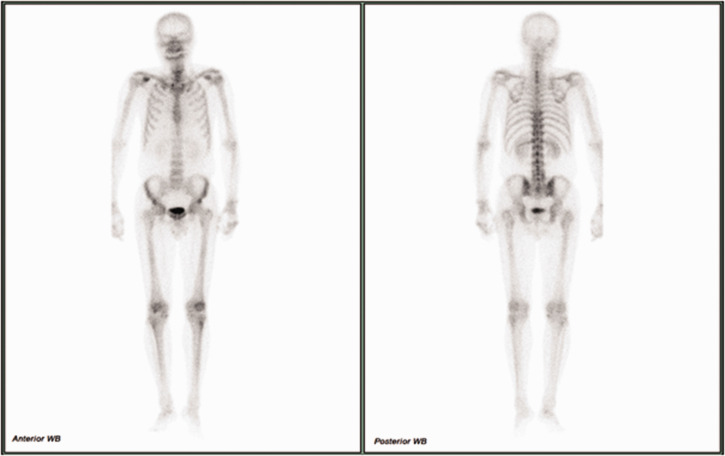

颈神经根病的发病率约为85 / 100000,其特点是颈神经根断裂引起疼痛。由于缺乏普遍接受的黄金标准,准确诊断具有挑战性,需要依赖患者病史、临床检查和诊断测试。臂丛神经转移是一种罕见但临床意义重大的疾病,可以模仿常见的肌肉骨骼疾病,如颈椎神经根病。其非特异性表现往往导致诊断延迟,特别是在癌症患者表现为持续上肢疼痛。本病例报告探讨了锁骨上臂丛转移的误诊,最初被误解为颈椎间盘突出,62岁男性肺癌病史。尽管接受了颈椎导管神经成形术和其他治疗,但患者持续的右臂疼痛促使进一步的调查。胸部计算机断层扫描和正电子发射断层扫描最终显示转移性鳞状细胞癌延伸至臂丛。该病例强调了对有癌症病史的患者进行全面诊断评估和考虑转移性肿瘤的关键需要。这也凸显了臂丛转移的罕见性和临床意义。它强调了综合护理方法的重要性,解决肿瘤和肌肉骨骼问题,以改善患者的预后。

Cervical radiculopathy, with an incidence of approximately 85 per 100,000 individuals annually, is characterized by pain originating from cervical nerve root disruption. Accurate diagnosis is challenging because of the absence of a universally accepted gold standard, necessitating reliance on patient history, clinical examination, and diagnostic tests. Brachial plexus metastasis is a rare but clinically significant condition that can mimic common musculoskeletal disorders, such as cervical radiculopathy. Its nonspecific presentation often results in delayed diagnosis, particularly in patients with cancer presenting with persistent upper-limb pain. This case report explored the underdiagnosis of supraclavicular brachial plexus metastasis, initially misinterpreted as cervical disc herniation in a 62-year-old man with a history of lung cancer. Despite undergoing cervical-Racz catheter neuroplasty and other treatments, the patient's persistent right arm pain prompted further investigations. Chest computed tomography and positron emission tomography computed tomography ultimately revealed metastatic squamous cell carcinoma extending to the brachial plexus. This case underscores the critical need for comprehensive diagnostic evaluations and the consideration of metastatic neoplasms in patients with a history of cancer. It also highlights the rarity and clinical significance of brachial plexus metastasis. It emphasizes the importance of an integrated approach to care, addressing both oncological and musculoskeletal issues to improve patient outcomes.